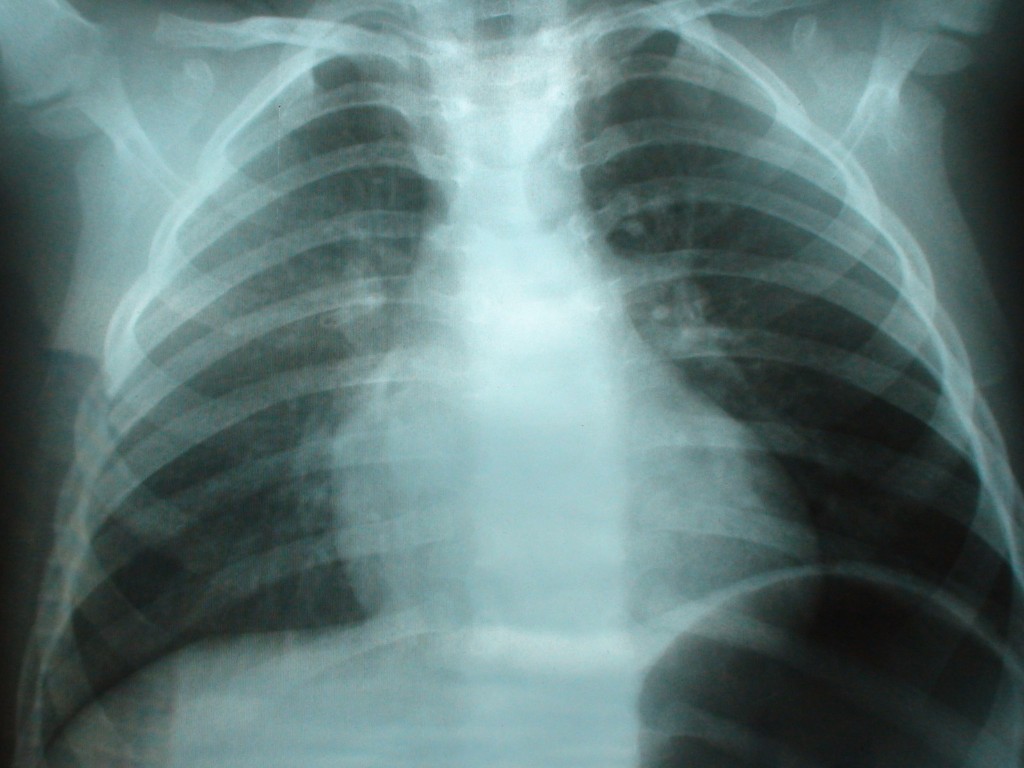

Снимок грудной клетки здорового ребенка: примеры и диагностика